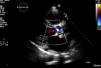

In March 2013 he began to experience fatigue, dyspnea on moderate and mild exertion, abdominal swelling, lower limb edema and cachexia. He was medicated with furosemide and ivabradine and assessed by a cardiologist four months after symptom onset. On physical examination he was in New York Heart Association (NYHA) class III, with marked weight loss and venous jugular distention; bilateral basal rales on pulmonary auscultation; rhythmic S1 and S2 on cardiac auscultation with a grade III/VI aortic early to mid systolic murmur radiating to the carotids; palpable hepatomegaly 4 cm below the costal margin; moderate ascites and lower limb edema up to the knee. The electrocardiogram showed sinus rhythm and complete right bundle branch block. On the chest X-ray cardiomegaly was visible with right atrial dilatation and bilateral hilar enlargement. Laboratory tests revealed anemia (hemoglobin [Hb] 9.9 g/dl). The echocardiogram showed dilatation of both atria and the right ventricle (RV) (Figure 1), with mild hypertrophy of the ventricular septum; a thickened and calcified aortic valve with significantly limited opening (Figure 2); peak left ventricular (LV)/aortic gradient of 55 mmHg, mean 33 mmHg, and functional aortic valve area of 0.8 cm2 (0.39 cm2/m2); mild to moderate tricuspid regurgitation (Figure 3) with pulmonary artery systolic pressure (PASP) of 51 mmHg; mild to moderate LV systolic dysfunction; systolic and diastolic straightening of the ventricular septum; and impaired RV systolic function.